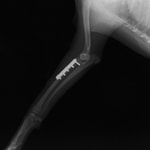

ペルシャ猫 11ヶ月齢 雄

他院にて左大腿骨遠位の成長板骨折(salter-harrisⅠ型)が認められており、治療相談を目的として来院。当院にて、キルシュナーワイヤーを用いたピンニングにより骨折部位の整復を行いました。術後の経過は良好で、現在も経過観察中です。

術後レントゲン

Arthrex社のターゲティングデバイスを用いてピンニングの位置を調整することで、確実な固定を行っています。当院ではこの手術器具以外にも、人の手術にも使用される様々な器具を導入し、手術精度を高め、また医療メーカーと新しい器具の開発、試作にも取り組んでおります。